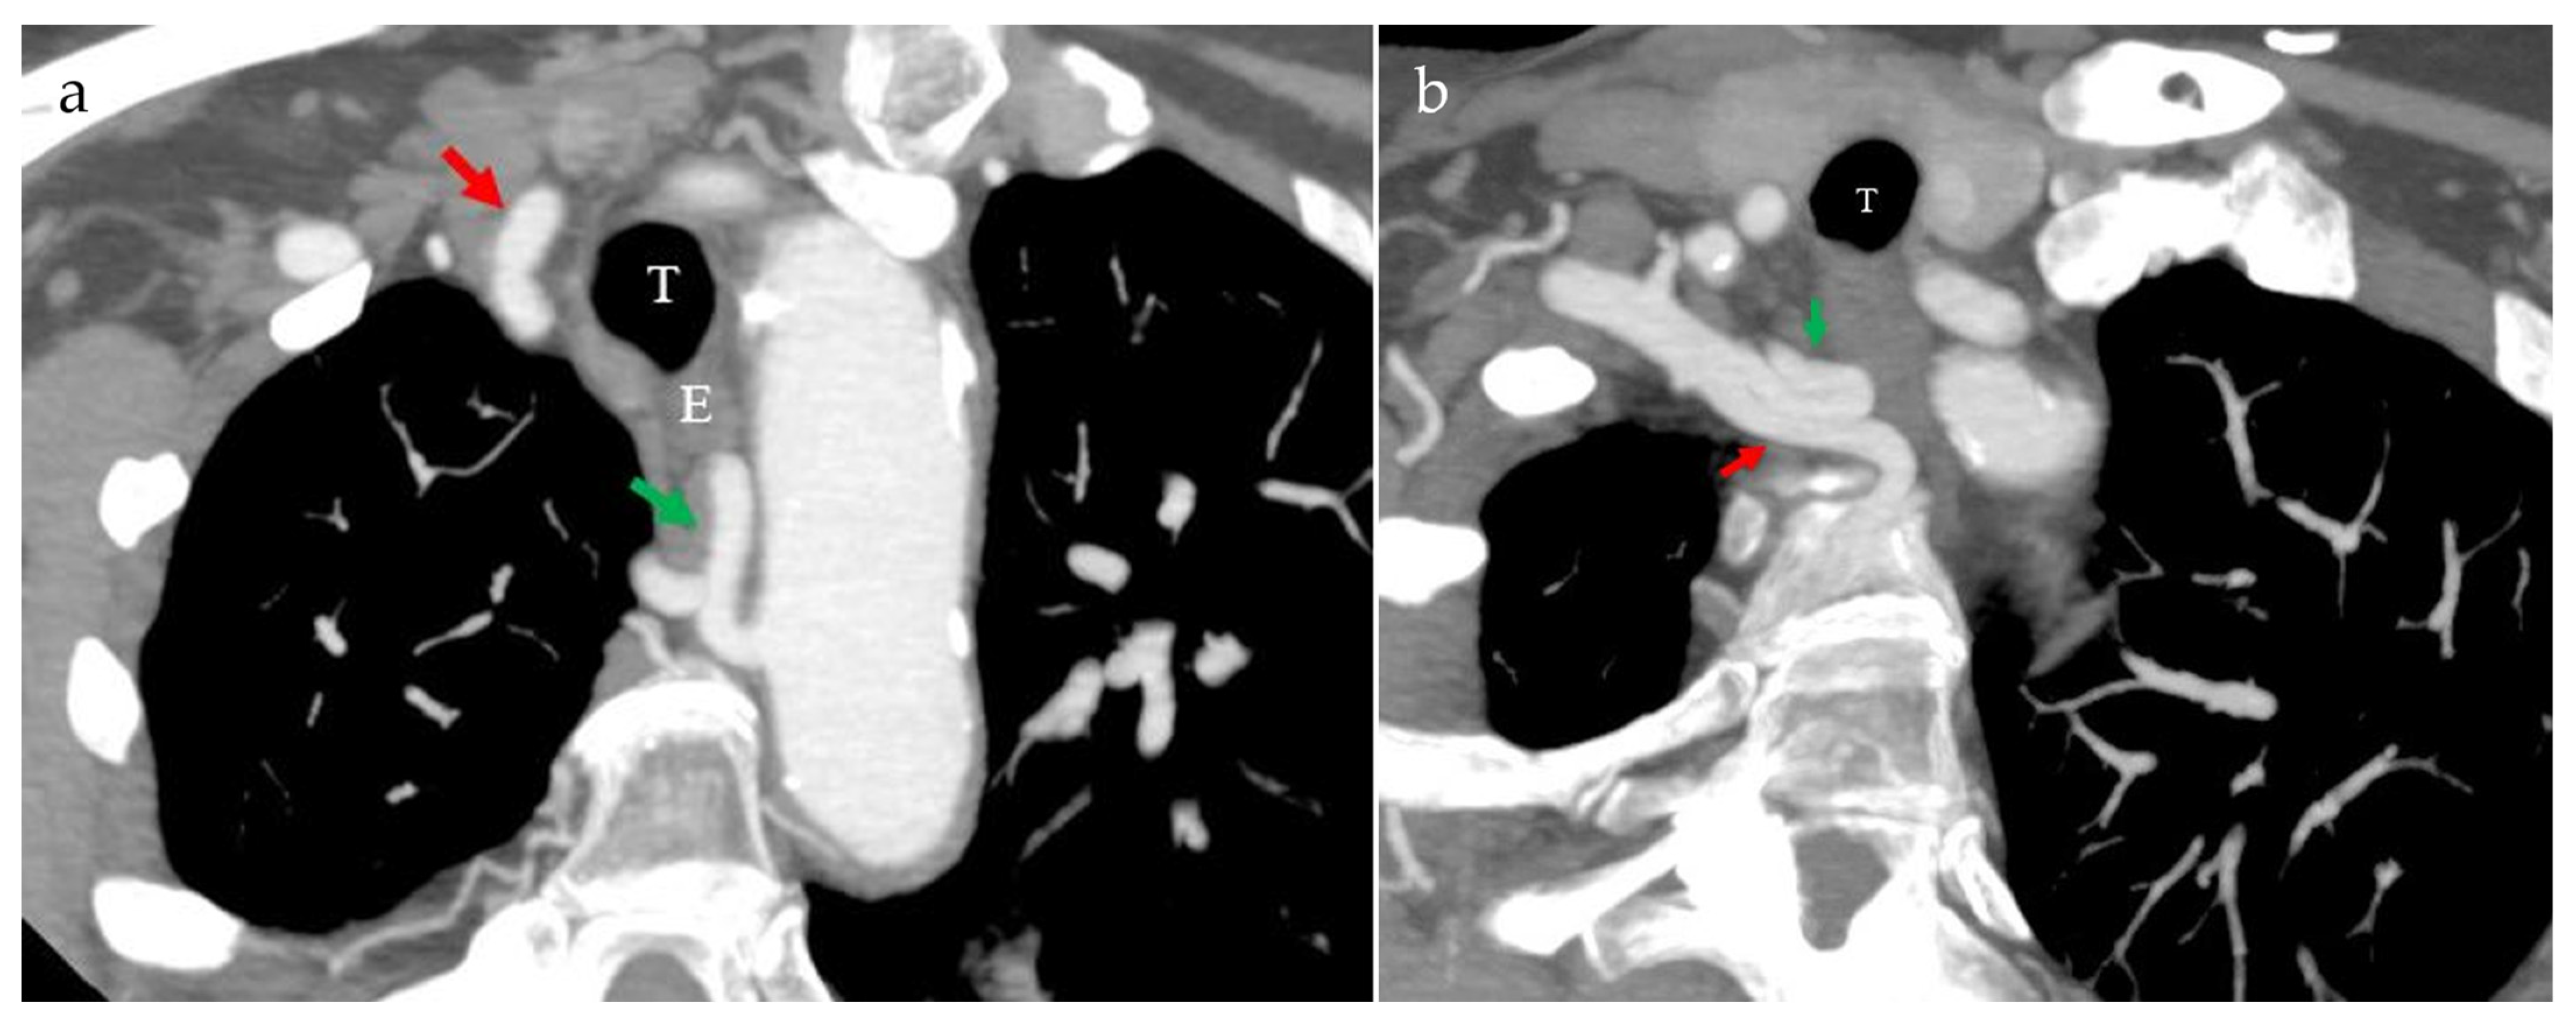

2. Case Presentation